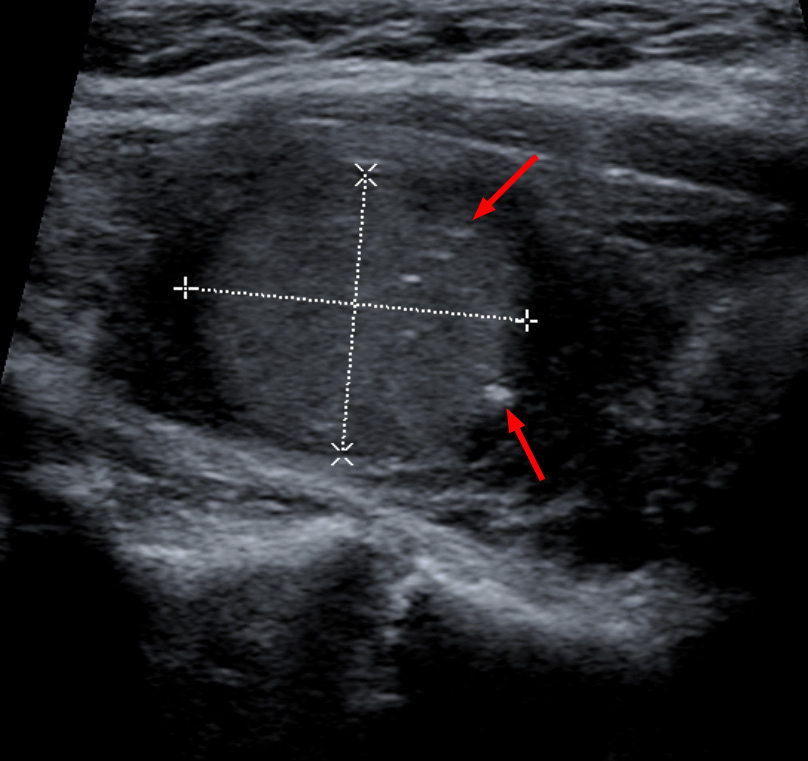

Злокачественная опухоль бартолиновой железы - фото презентация